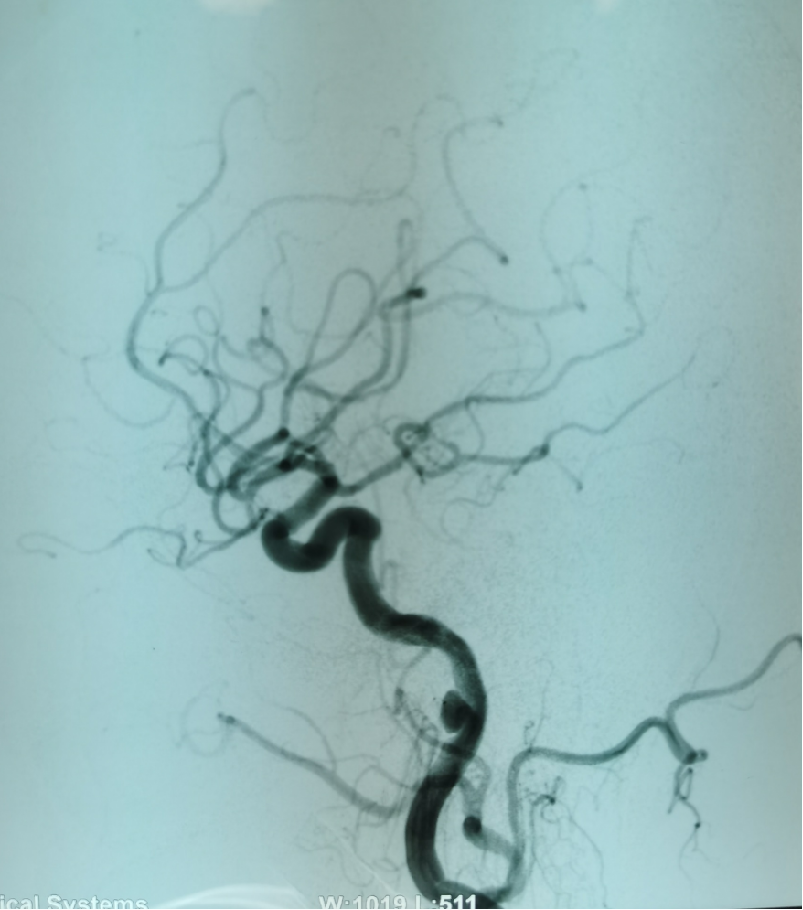

患者赵某某,男,70岁,因突发左侧肢体活动不灵3小时入院,查体:神志模糊,反应迟钝,言语不清,左侧鼻唇沟变浅,口角右侧偏斜,左侧肢体肌力0级,右侧肢体肌力正常,双侧巴氏征阴性。入院颅脑CT示腔隙性脑梗死。主治医师魏华明建议急诊取栓治疗。手术由魏华明主治医师操作,10分钟完善术前准备,5分钟完成脑血管造影,考虑为右侧夹层动脉瘤所致急性期脑梗死,夹层内有急性血栓形成,血栓有进一步加重的可能性,同时夹层有急性撕裂破裂的可能性,病情非常凶险。神经介入团队仅用时30分钟成功为患者实施颈动脉支架植入血管成形术,同时给予尿激酶动脉溶栓,患者左侧肢体肌力立即恢复至3级。术后,经过神经内一科医护团队的精心治疗和严密护理,现患者左侧肢体肌力已恢复至四级。

右侧夹层动脉瘤